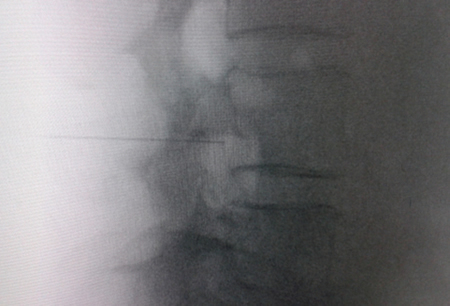

(Figuras 1 y 2) pero la localización final será determinada por la estimulación nerviosa sensitivo-motora. La estimulación sensitiva consiste en provocar parestesia o dolor en el territorio afectado con una estimulación entre 0,3-0,6 v. Durante la estimulación motora se pueden provocar fasciculaciones en el territorio afectado con un voltaje del doble al necesario para provocar las parestesias. Si se desea realizar una denervación intraganglionar, promulgada por algunos autores, la estimulación tanto sensorial como motora será positiva a menos de 0,3 v. Por tratarse de un procedimiento más doloroso, se aconseja administrar anestésicos locales después del estímulo doloroso y antes de realizar el tratamiento. La impedancia deberá mantenerse por debajo de 450 ohms, lo que se consigue infundiendo solución salina previa a la RF (4). La utilización de contraste constituye una buena práctica, ya que descarta la posición intravascular e intratecal de la cánula de radiofrecuencia.

Fig. 2. Imagen radiológica anteroposterior de una cánula de radiofrecuencia posicionada en neuroforamen L4-L5, en el llamado triángulo de seguridad, después de la inyección de contraste. Se observa un engrosamiento del radiculograma a nivel del techo del neuroforamen, que podría corresponder al ganglio de la raíz dorsal de L4